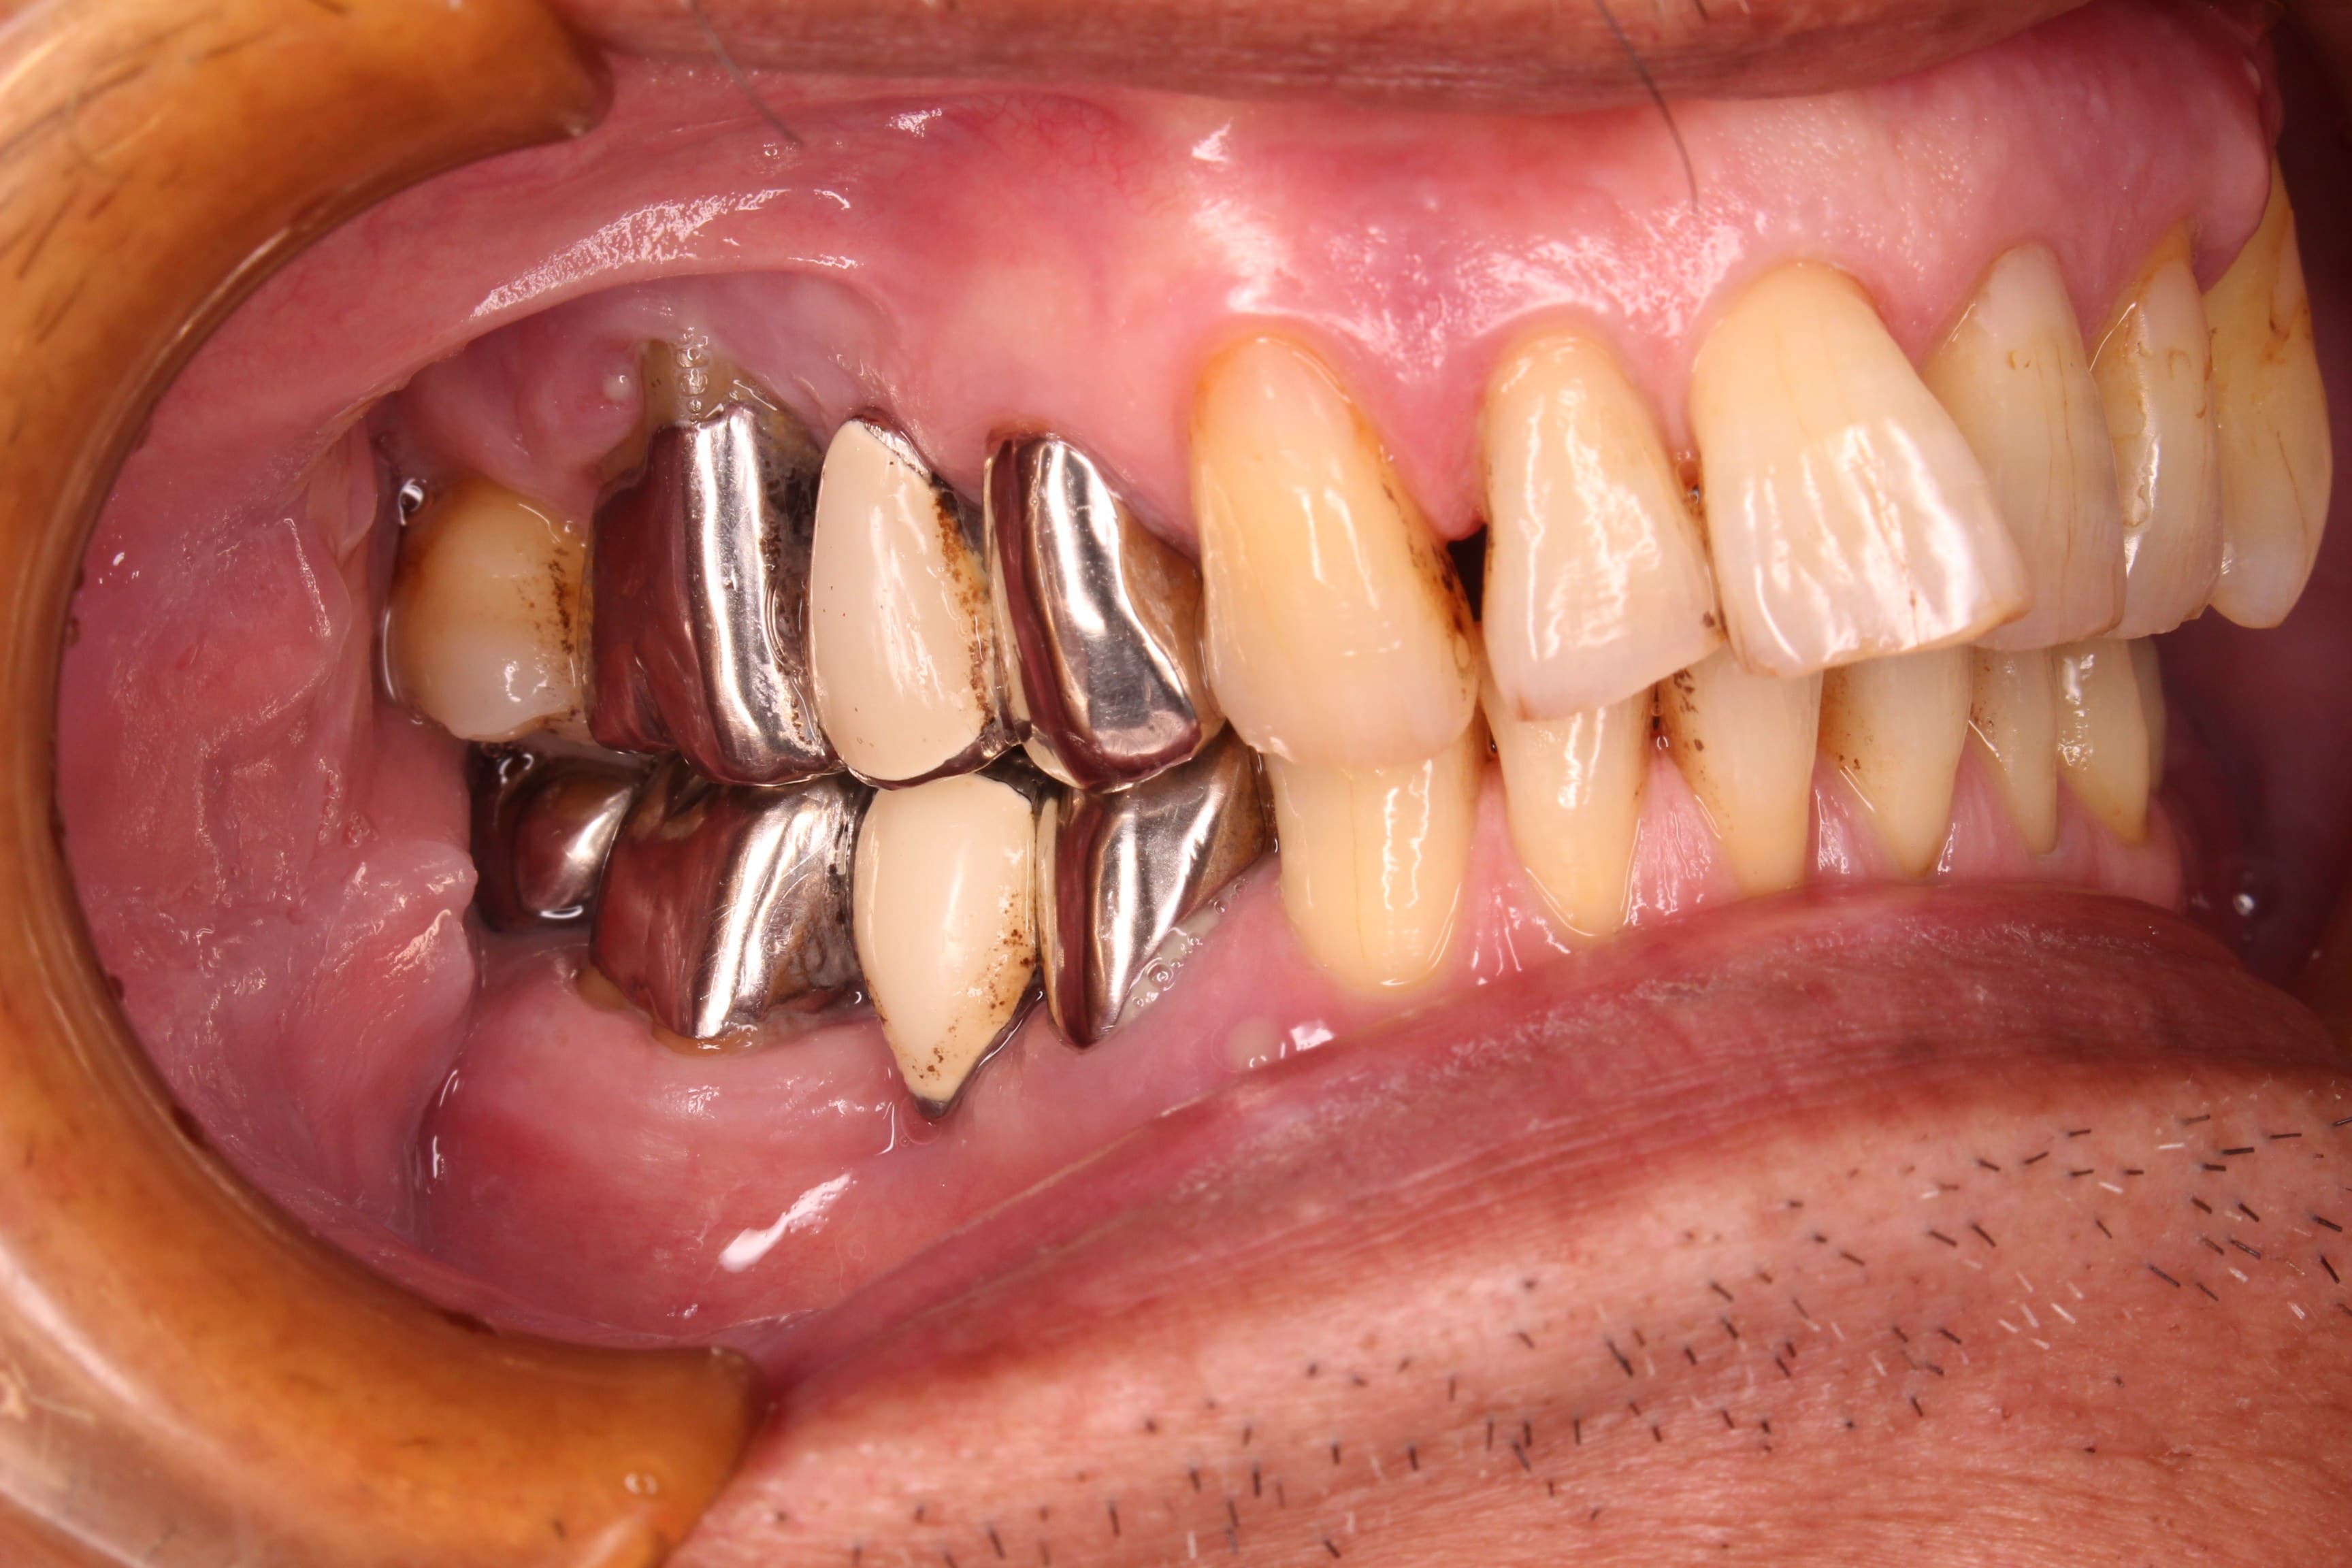

初診時

歯周専門治療後